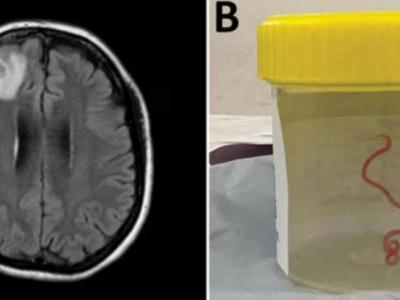

Sydney, Aug 29 In a world's first such case, a team of Australian neurosurgeons has removed an eight cm-long parasitic roundworm from a patient who complained of forgetfulness and depression.

The world's first case of a new parasitic infection in humans was discovered by researchers at The Australian National University (ANU) and the Canberra Hospital after they detected a live roundworm from a carpet python in the brain of a 64-year-old Australian woman.

The Ophidascaris robertsi roundworm was pulled from the patient after brain surgery -- still alive and wriggling. It is suspected larvae, or juveniles, were also present in other organs in the woman’s body, including the lungs and liver.